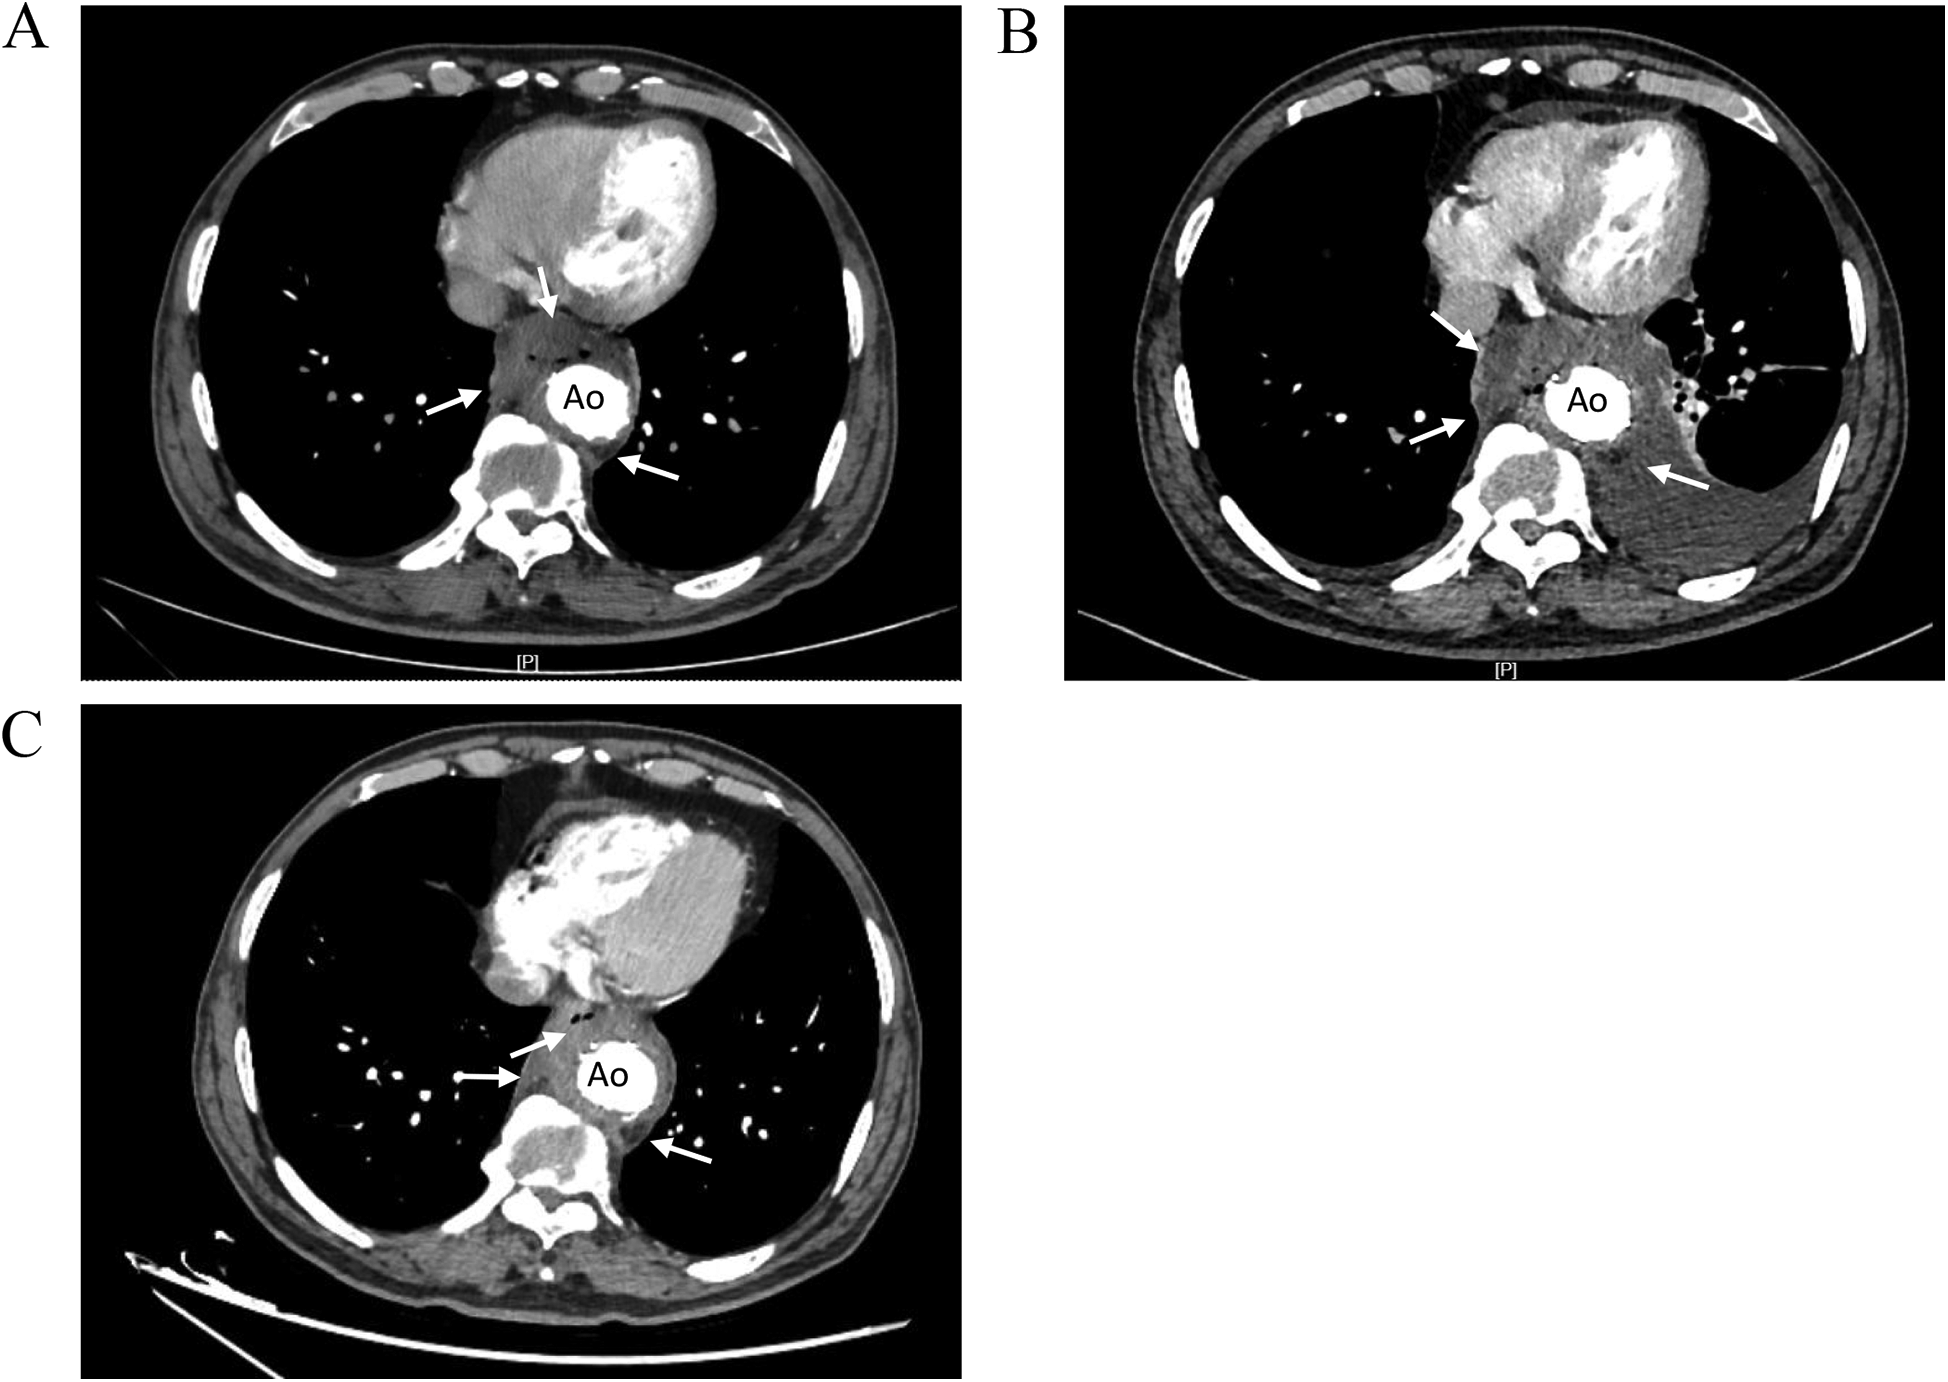

The patient had recurrent fever for 6 months, After the second admission, and CTA still revealed a mass lesion around the stent. Aortic endograft infection was considered. piperacillin-tazobactam [4.5, ter in die, intravenous drip (TID, iv. D)] and tigecycline [0.05, bis in die, intravenous drip (BID, iv. D)] were given for anti-infective treatment. CTA imaging of the thoracic aorta revealed that after thoracic aortic stenting, there was a mass lesion around the lower thoracic aortic stent and the esophageal area with air accumulation. Compared with the previous CTA of the thoracic aorta, the lesion was enlarged in the right anterior area and slightly reduced in the left posterior area, with bilateral pleural effusions and partial atelectasis in the adjacent lower lobe of the left lung. After anti-infective treatment, the patient had no fever, and the infection index decreased. After multidisciplinary consultation with the Departments of Cardiac Surgery, Vascular Surgery, and Infectious Disease, it was considered that the patient had an aortic graft infection involving the esophagus and that surgical treatment was needed; however, the risk of surgery was high, and the patient chose to continue conservative treatment. Minocycline [0.1, bis in die, per os (BID, p.o.)] and amoxicillin [0.5, ter in die, per os (TID, p.o.)] were recommended after discharge. The patient returned to the hospital for reexamination 3 months after discharge, and there was no fever or other symptoms of discomfort. CTA of the thoracic aorta revealed a mass lesion around the stent in the lower thoracic aorta and the esophageal area with air accumulation, although it was significantly smaller than that previously observed (Figure 2).

Figure 2

Comparison of thoracic aortic CTA images showing. (A) CTA images 2 months before admission. Low-density shadow was found around the stent in the lower thoracic aorta (right side, right anterior, left posterior), and the boundary with the esophagus was not clear. (B) CTA images during hospitalization. The low-density shadow around the stent in the lower thoracic aorta had unclear boundary with the esophagus, accompanied by air in it, and the scope of the lesion was larger than before. (C) CTA images at 3 months after discharge. The mass lesion around the lower thoracic aortic stent with air accumulation in it, the range of infection was smaller than before. Ao, descending thoracic aorta.